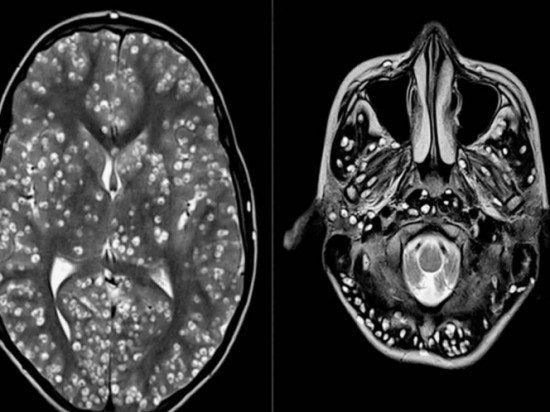

Tras practicarle una resonancia magnética, los especialistas encontraron que la corteza cerebral y el tronco encefálico del paciente estaban llenos de larvas

Tras practicarle una resonancia magnética y exámenes de ultrasonido, los especialistas encontraron que la corteza cerebral y el tronco encefálico del paciente estaban llenos de larvas.

El muchacho padecía neurocisticercosis, una enfermedad parasitaria originada cuando una persona ingiere huevos microscópicos de una tenia porcina y que afecta al tejido muscular. De ahí los parásitos se propagan al cerebro. Los personas infectadas pueden pasar mucho tiempo sin presentar síntomas.

A pesar de que esta afección se puede tratar con medicamentos, el elevado número de quistes no permitió al chico que se le suministraran los fármacos antiparasitarios necesarios.

El paciente fue tratado con corticoides estándares y medicamentos para evitar que se le manifestaran ataques epilépticos. Sin embargo, no se pudo revertir la situación y murió dos semanas después.